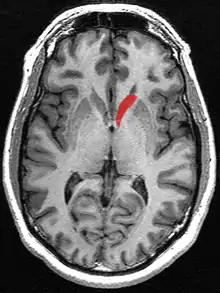

![]() Caudate nucleus (in red) shown within the brain | |

The caudate nucleus is one of the structures that make up the corpus striatum, which is a component of the basal ganglia in the human brain.[1] While the caudate nucleus has long been associated with motor processes due to its role in Parkinson's disease,[2][3] it plays important roles in various other nonmotor functions as well, including procedural learning,[4] associative learning[5] and inhibitory control of action,[6] among other functions. The caudate is also one of the brain structures which compose the reward system and functions as part of the cortico–basal ganglia–thalamic loop.[1]

Together with the putamen, the caudate forms the dorsal striatum, which is considered a single functional structure; anatomically, it is separated by a large white matter tract, the internal capsule, so it is sometimes also referred to as two structures: the medial dorsal striatum (the caudate) and the lateral dorsal striatum (the putamen). In this vein, the two are functionally distinct not as a result of structural differences, but merely due to the topographical distribution of function.

The caudate nuclei are located near the center of the brain, sitting astride the thalamus. There is a caudate nucleus within each hemisphere of the brain. Individually, they resemble a C-shape structure with a wider "head" (caput in Latin) at the front, tapering to a "body" (corpus) and a "tail" (cauda). Sometimes a part of the caudate nucleus is referred to as the "knee" (genu).[7] The caudate head receives its blood supply from the lenticulostriate artery while the tail of the caudate receives its blood supply from the anterior choroidal artery.[8]